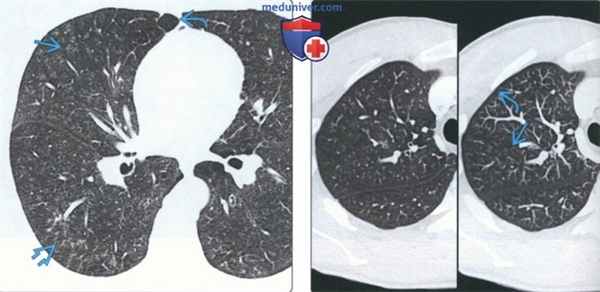

(Слева) На аксиальной КТВР у женщины 29 лет с респираторным бронхиолитом, злоупотреблявшей курением смеси табака и кокаина (известной как «базуко»), визуализируются центрилобулярные очаги с плотностью «матового стекла», очаги в виде «дерева в почках» на фоне эмфиземы.

(Справа) На аксиальной КТ с КУ (слева) и аксиальной MIP (справа) у пациента с респираторным бронхиолитом визуализируются центрилобулярные очаги с плотностью «матового пекла», наиболее заметные на MIP. Обратите внимание, что субплевральные отделы легких интактны (очаги расположены центрилобулярно).

3. КТ легких при респираторном бронхиолите:

• КТВР:

о Микроузелки:

- Распределение:

Центрилобулярное

Субплевральные отделы и междольковый интерстиций интактны

- Плотность:

«Матовое стекло»

- Контуры:

Нечеткие

- Могут исчезать или сохраняться после отказа от курения

о MIP улучшает визулизацию микроузелков

о Зоны «матового стекла»:

- Диффузные

- С преимущественным поражением верхних долей

о Экспираторная КТ:

- Дольковые воздушные «ловушки»

о Утолщение стенок центральных и периферических бронхов